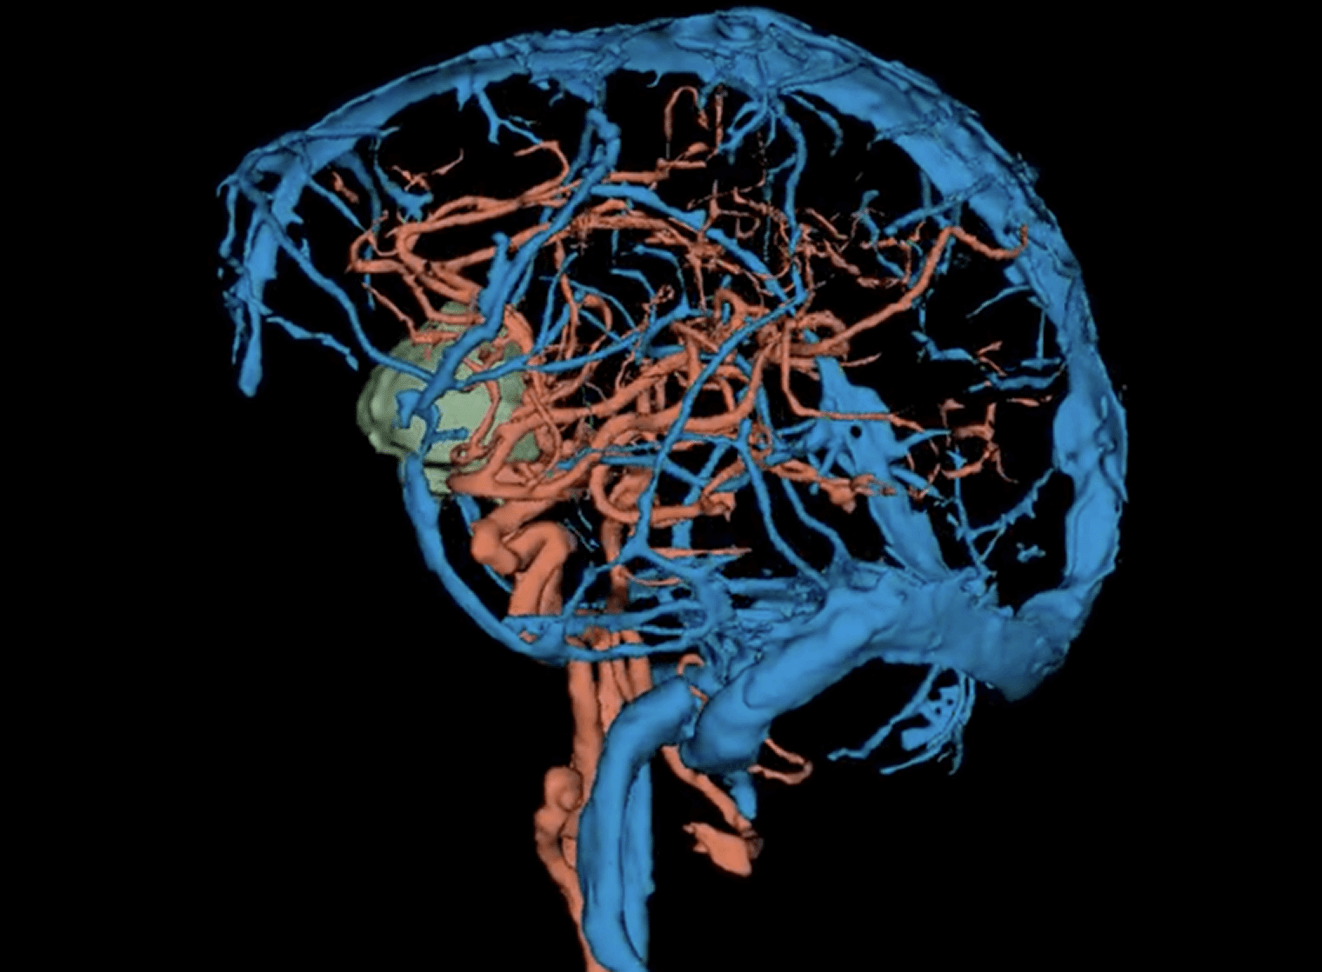

We are a labeling company

specializing in radiology, pathology, cardiology, internal medicine, and surgery. We label data and offer software development for image labeling.

MD, Radiologist, Co-Founder. US board certified Harvard trained neuroradiologist with decades of private practice experience

MD, Radiologist, and Project Manager specializing in AI applications in medical visualization, with expertise in medical data labeling